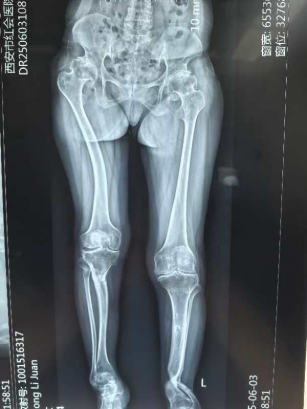

MED是一种罕见的遗传性骨软骨发育障碍疾病,发病率约为1/10万,约50%的MED病例呈家族性发病。由于全身多部位骨骺软骨发育异常,常表现为多关节畸形、疼痛及活动受限,基因检测及影像学动态监测对早期诊治至关重要。

该患者其有明确家族史,结合患者病史、查体、影像学检查及基因检测结果确诊MED。该患者髋、膝、踝关节均存在明显畸形,前期在当地医院已行胫骨截骨矫形手术,目前以右髋关节疼痛为主,需行全髋置换手术治疗。由于患者术前髋部病变严重且合并股骨近端畸形,术中需特别注意臼杯安装角度及股骨柄植入方向,虽然DAA全髋置换手术难度大,但是能更少的损伤髋部软组织,术后体位无限制,患者早期康复锻炼效果更好。患者右侧肢体短缩,术中尽量延长患肢以改善下肢不平衡,使其能更快地回归正常生活、工作,充分体现了医疗团队的技术和对患者全面关怀的人文理念。